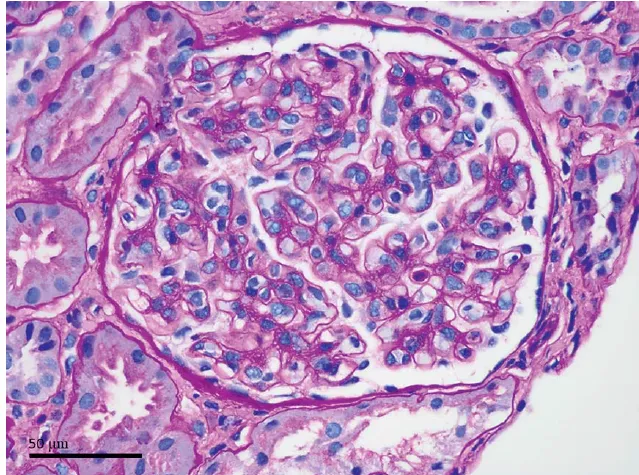

Foi feito o diagnóstico de microcistos compatíveis com nefropatia induzida por lítio. O uso de lítio está associado a diversos efeitos nefrotóxicos, incluindo diabetes insipidus nefrogênico, acidose tubular renal e nefropatia túbulo-intersticial crônica.

Microcistos de 1 a 2 mm podem ser observados em exames de imagem em pacientes com nefropatia túbulo-intersticial crônica induzida por lítio. O paciente permaneceu em tratamento com agentes alternativos para o transtorno bipolar. Após 2 anos de seguimento, a função renal manteve-se estável.